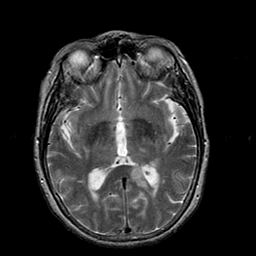

Stroke:T2-weighted MR #1 -- Slice #12

[Home][Help][Clinical] Slice 12